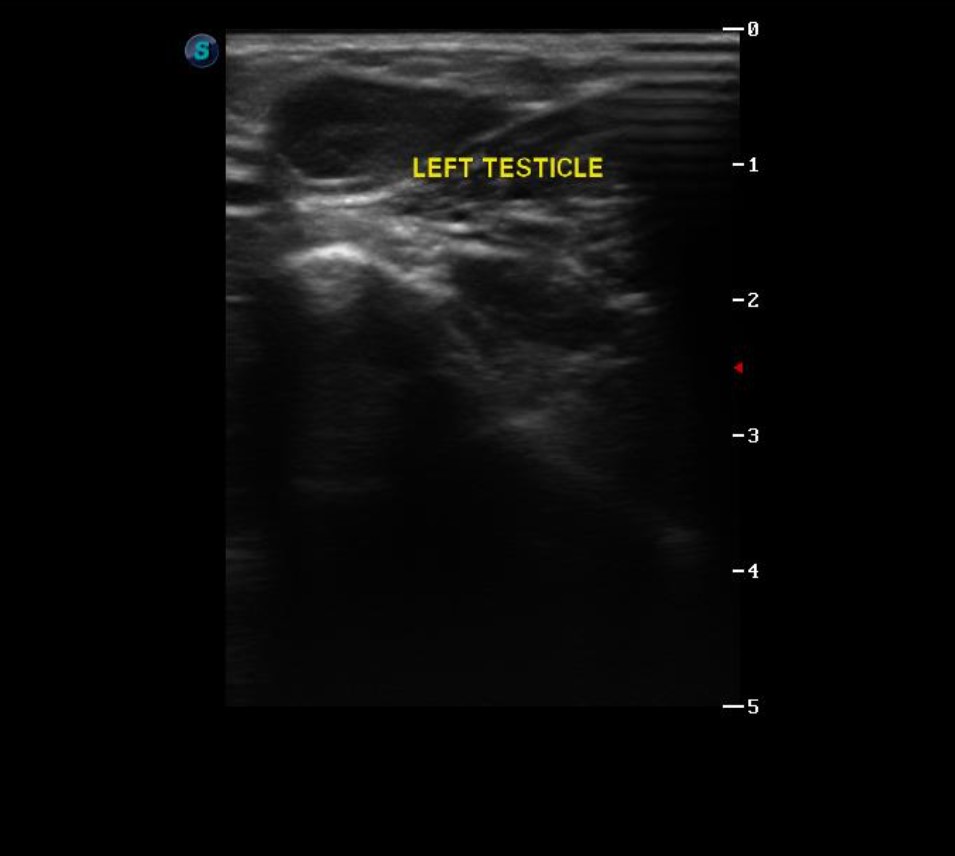

초음파 - 촉진으로 고환을 찾을 수 없는 경우 고환의 위치를 파악하기 위하여 초음파를 사용합니다.

촉진으로 대략적인 위치를 파악한 후 초음파로 확인하고 수술을 진행하였습니다.